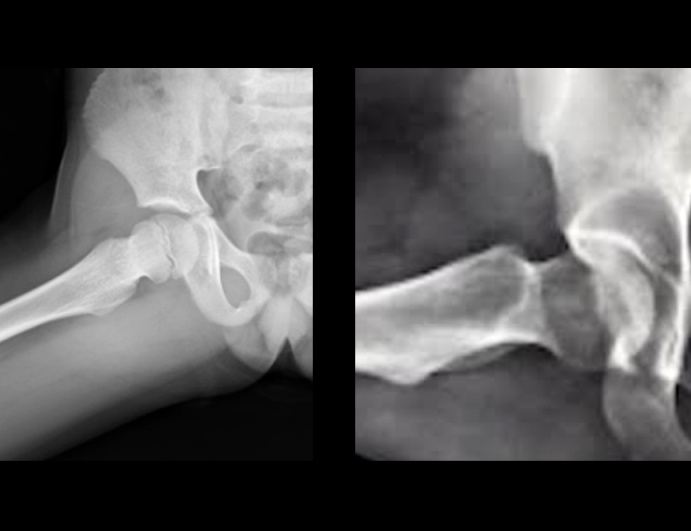

>それはただのシワだろう

普通こんな断裂映るわけがない

fu6179727.jpg

>普通こんな断裂映るわけがない

多分否定してる「」は答えられないから俺が答えるが大腿骨頭にくっついてる大腿骨頭靭帯じゃろう

fu6179744.jpg

>fu6179727.jpg

左は成長期の股関節じゃないか

左のは骨端線で骨折ではない

これ何

fu6179770.jpg

4326/01/18(日)00:55:57No.1393493648+

それはただの肉の皺というか関節

>これ何

>fu6179770.jpg

肉が盛りあがって段になってるだけ

デブとかよくこうなる